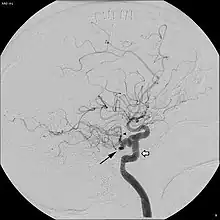

Angiogram demonstrating persistent trigeminal artery, as indicated by the black arrow.